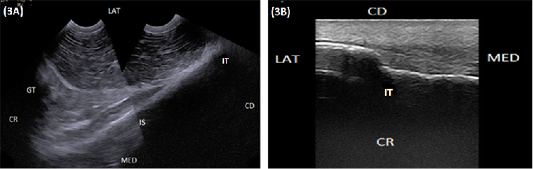

(A) Compound longitudinal sonogram (6.6 MHz micro convex probe, 11 cm depth) in a 6-year-old cow showing the ischium (IS), ischial tuber (IT), greater trochanter (GT). CR, Lateral direction (LAT), medial direction (MED), cranial direction (CR) and caudal direction (CD). (B) longitudinal sonogram (10 MHz linear tendon probe, 5 cm depth) in an 8-year-old cow showing ischial tuber (TI), lateral direction (LAT), medial direction (MED), cranial direction (CR) and caudal direction (CD).